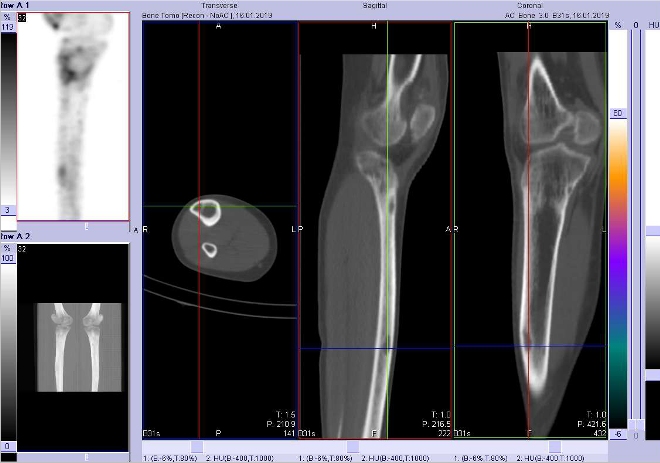

Celotělové scintigramy (obr.3) jsme provedli po podání 700 MBq

99mTc-oxidronátu (přípravek TechneScan HDP firmy Mallinckrodt Medical) na hybridní tomografické scintilační kameře Symbia T2 firmy Siemens. Vyšetření jsme doplnili o cílenou tomografickou scintigrafii (SPECT) kombinovanou s CT kolenních kloubů a přilehlé části stehenních kostí a kostí bérců

(obr. 4-11).

/ Obr. č. 7: Fúze obrazů SPECT a CT. Zaměřeno na ložisko v diafýze pravé tibie. Řez transverzální, sagitální a koronální.

/

/ Obr. č. 8: Fúze obrazů SPECT a CT. Zaměřeno na ložisko v diafýze pravé tibie. Řez transverzální, sagitální a koronální.

Popis: Tři ložiska lehce vyšší osteoblastické aktivity v pravé tibii – dvě v proximální části a třetí je v diafýze zhruba uprostřed laterálně. Tato ložiska jsou na ldCT oválného tvaru v kortikalis povrchově s výrazně sníženou denzitou (osteolytická), kortikalis je poněkud ztenčená. S velkou pravděpodobností se jedná o neosifikující fibromy.